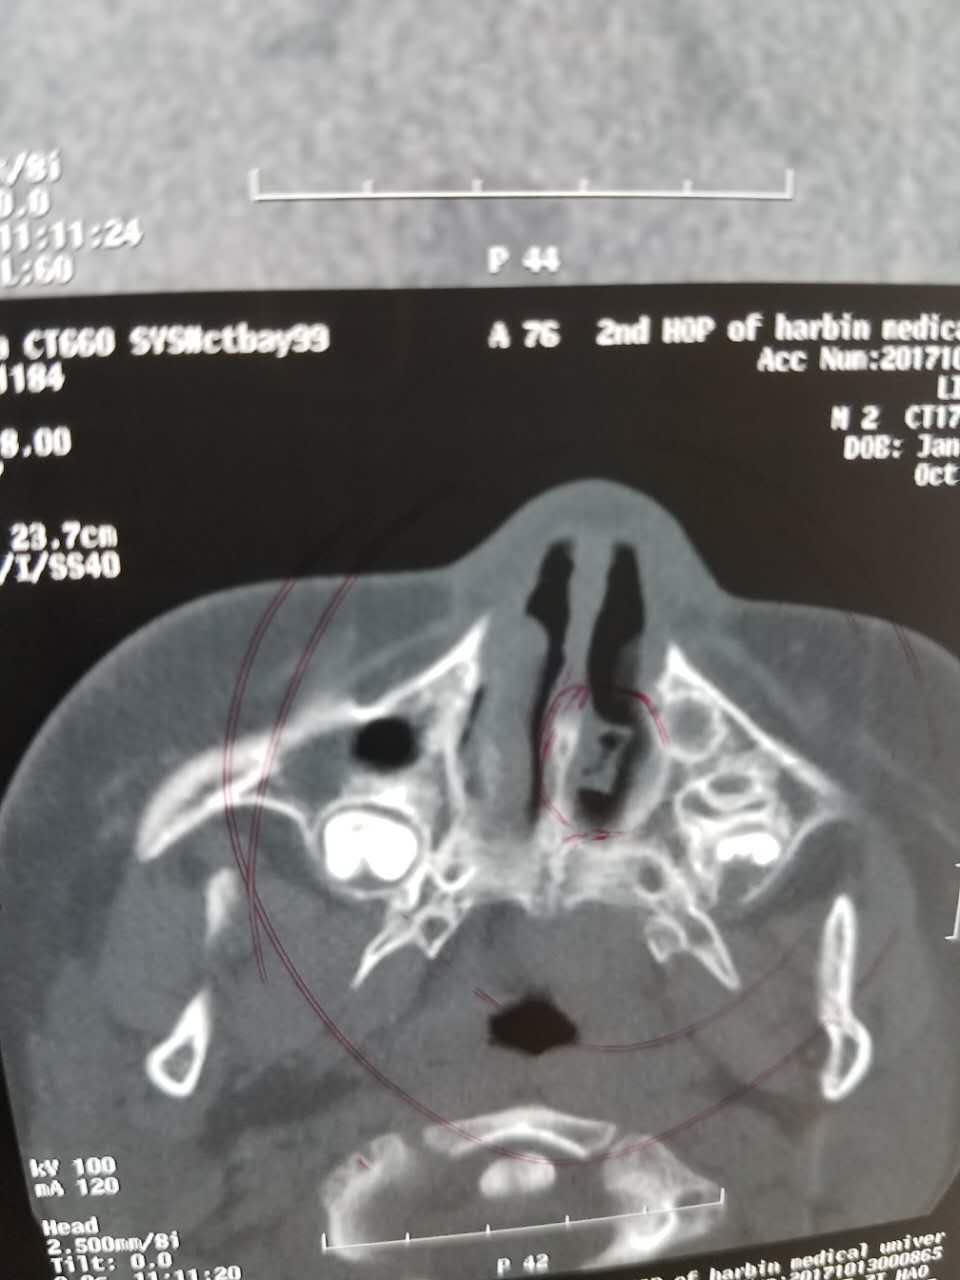

鼻部异物

鼻塞及鼻腔可闻及臭味

鼻窦ct可见如上

鼻腔异物,在鼻内镜下予以取出